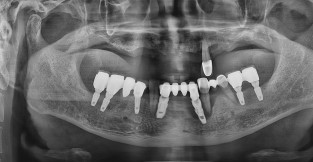

• 1

전체 임플란트

치료기간 : 2024-03-06 ~ 2024-09-17

1. 상기 x-ray 이미지 모두 동일한 해당 의료기관에서 진료한 환자입니다.

2. 상기 x-ray 이미지 모두 동일 인물의 것입니다.

3. 치료 전 이미지는 2024-03-06에 촬영했으며, 치료 후 이미지는 2024-09-17에 촬영하였습니다.

4. 상기 x-ray 이미지 모두 동일 조건에서 환자분의 동의를 받아촬영되었습니다.

* 임플란트 시술은 환자분의 상태(고혈압, 당뇨 등)에 따라 부작용이 있을 수 있으니, 반드시 전문의와 상담이 필요합니다.

* 임플란트 수술 부작용

: 수술 후 출혈, 교합, 통증, 붓기, 염증 등의 문제점이 발생할 수 있습니다.)